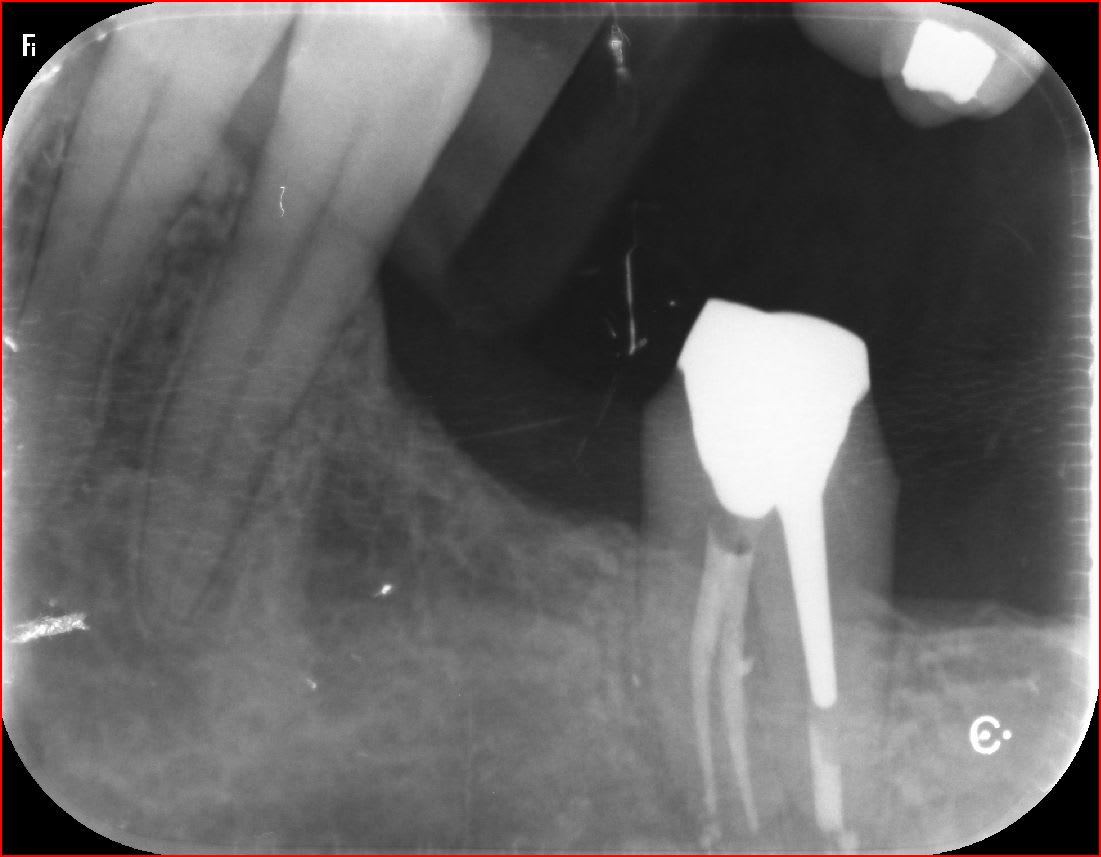

oh putaing qu'est ce que je fais ?

- j'ai déjà posé des implants sur ce patient et l'os c'est du béton armé donc pas d'ERI sinon la racine va casser

- tout le 1/3 apical est calcifié , impossible de passer le moindre instrument

- du coup je lui recrée un canal au milieu avec mes inserts :))

Bin moi Junior quand je grossis la radio post op, je vois une fracture milieu de racine mais je dis ça, jdis rien :)))

Non a mon avis c est un artefact numerique.

T'es sûr ??? car ça ne concerne que cette dent et avec des inserts c'est possible, nan ???